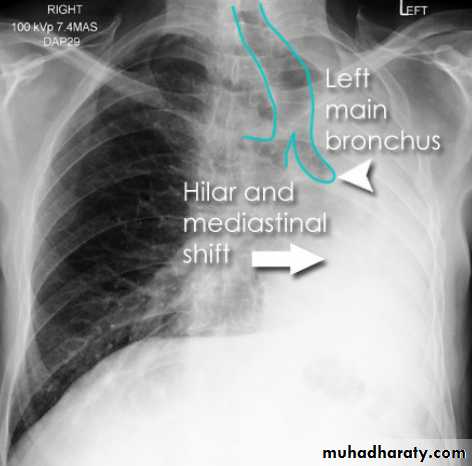

Left upper lobe collapse has distinctive features but can be challenging to identify on chest radiographs by the uninitiated.

Radiographic features

The left upper lobe collapses anteriorly becoming a thin sheet of tissue apposed to the anterior chest wall, and appears as a hazy or veiling opacity extending out from the hilum and fading out inferiorly . It thus reverses the normal slight increase in radiographic density seen as you move down the lung (due to increased thickness of the chest soft tissues).

Parts of the normal cardiomediastinal contour may also be obliterated where the left upper lobe, particularly the lingula abut the left heart border. The anterior parts of the aortic arch are also often obliterated from view.

In some cases the hyperexpanded superior segment of the left lower lobe insinuates itself between the left upper lobe and the superior mediastinum, sharply silhouetting the aortic arch and resulting in a lucency medially. This is known as the HYPERLINK "http://radiopaedia.org/articles/luftsichel-sign" luftsichel sign.

The left hilum is also drawn upwards, resulting in an almost horizontal course of the left main bronchus and vertical course of the left lower lobe bronchus.

Non-specific signs indicating left sided atelectasis will also be present, including:

elevation of the hemidiaphragm

'peaked' or 'tented' hemidiaphragm: HYPERLINK "http://radiopaedia.org/articles/juxtaphrenic-peak-sign" juxtaphrenic peak sign

crowding of the left sided ribs

shift of the mediastinum to the left

On lateral projections the left lower lobe is hyperexpanded and the oblique fissure displaced anteriorly. There is associated increase in the retrosternal opacity.